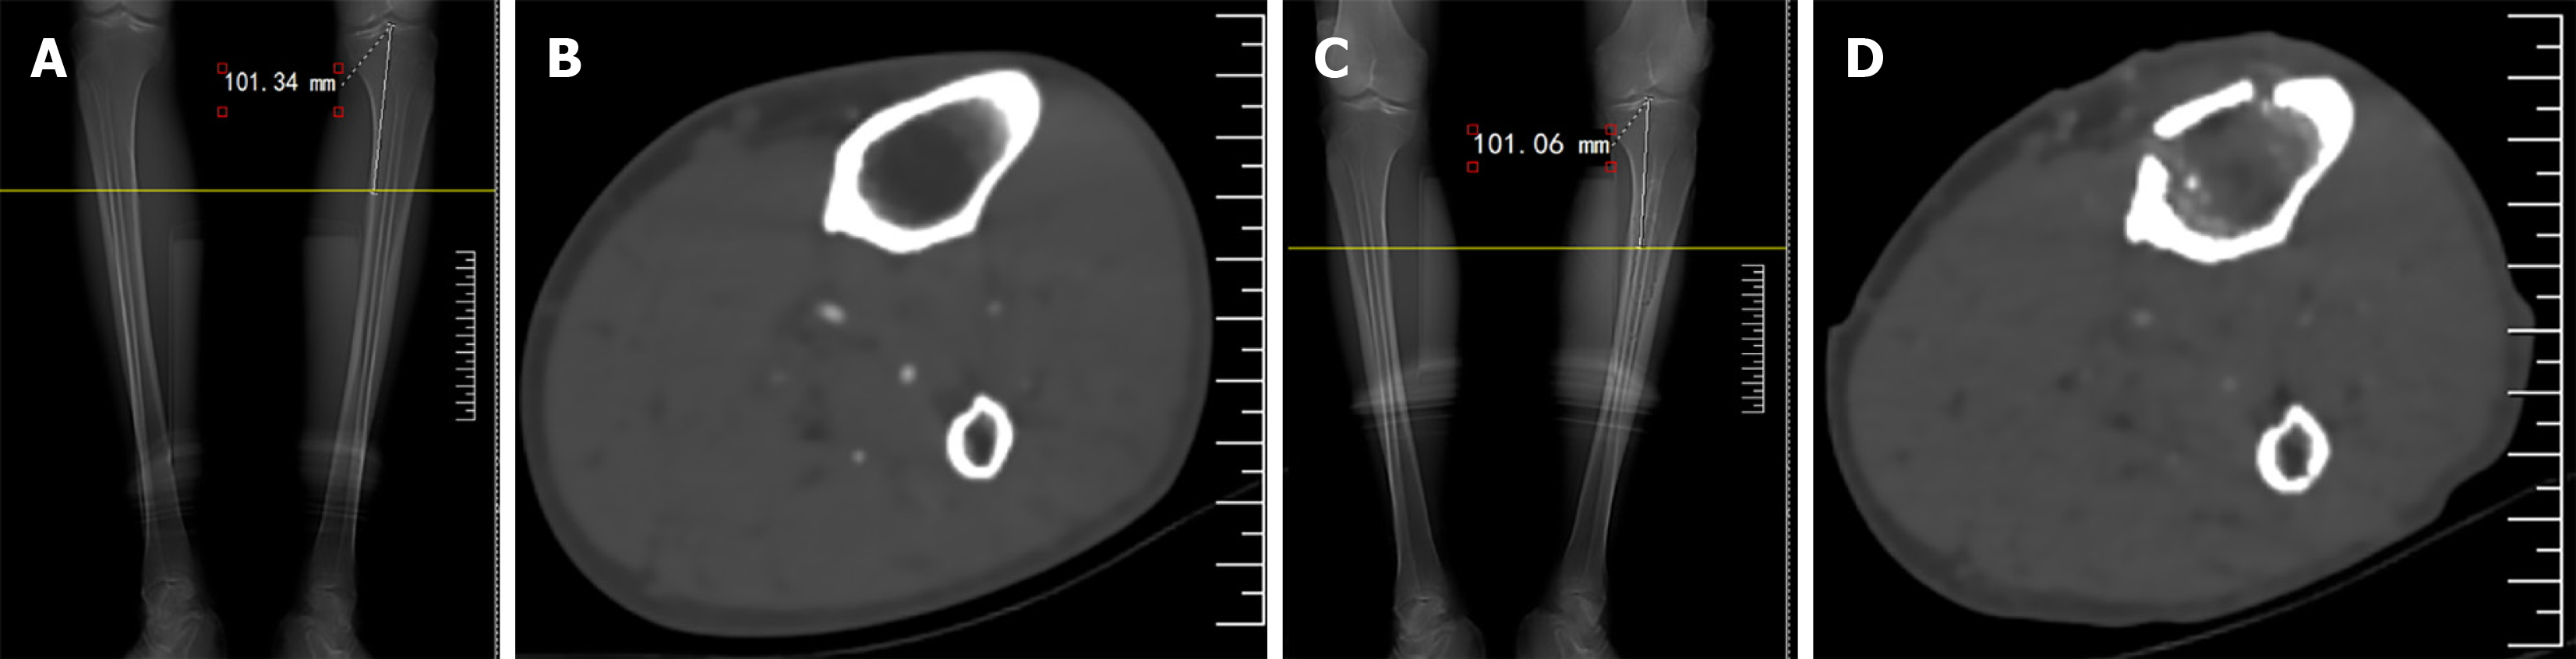

Figure 2 An elderly male patient with left diabetic foot (Wagner’s grade 4) underwent transverse tibial bone transport.

A: Computed tomography (CT) examination demonstrated a large quantity of new bone in the medullary cavity corresponding to the bone transport block one month after the operation; B: A large quantity of new bone in the medullary cavity 1 month after the operation; C: CT examination showed leg bone morphology; D: There was scarce bone in the corresponding part of the medullary cavity before the operation.